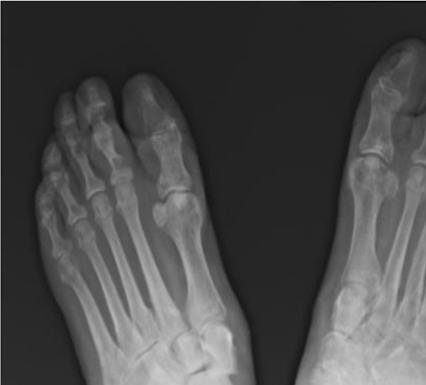

921 Charcot Neuroarthropathy of the Foot and Ankle in the Acute Setting: An Illustrative Case Report and Targeted Review

Kian Bagheri, Albert T. Anastasio, Alexandra Krez, Lauren Siewny, Samuel B. Adams